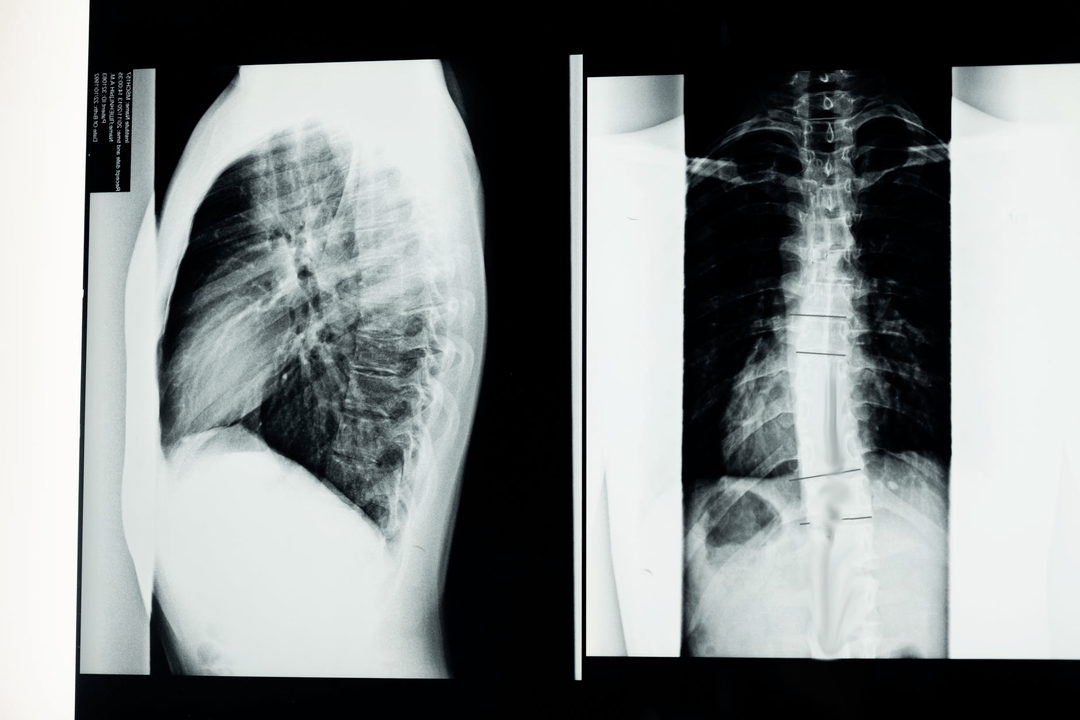

Before starting diagnostic studies, the neurologist collects the patient's medical history and carefully studies his ailments.Osteochondrosis has symptoms common to some other diseases, so it is important to be able to differentiate the pathologies.X-ray studies will help confirm the diagnosis of osteochondrosis: radiography, myelography and computed tomography.

A survey x-ray allows you to obtain an x-ray image of the spine or a section of it.In this way, the doctor can determine the site affected by the disease.For clarity we will explain how osteochondrosis can be determined by X-ray: the image will show a narrowing of the intervertebral disc, the presence of bone growths (osteophytes) or a change in the shape of the spinal segment.